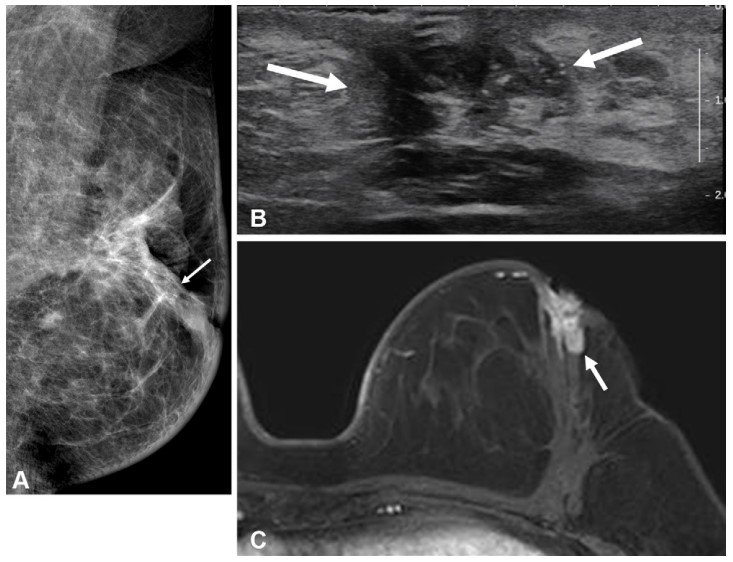

수술 후 같은 측 유방 내 재발이 발생한 젊은 유방암 환자의 검사 결과. 서울대병원 제공

유방암은 호르몬 수용체 유무에 따라 재발 양상이 다르며, 특히 호르몬 수용체 음성 유방암은 양성 대비 재발률이 높다. 50세 이하 유방암 환자는 유방 조직이 치밀한 경우가 많아 조기 진단이 어려울 뿐 아니라 호르몬 수용체 음성 유방암 발생률이 높다. 또 수술 후 같은측 유방 내 재발(국소 재발) 가능성도 높기 때문에 정확한 진단과 최적화된 수술을 위해 수술 전 ‘유방 MRI’ 사용이 증가하는 추세다.

유방 MRI는 유방암 검사 중 가장 민감도가 높아 유방촬영술과 초음파에서 놓친 종양도 탐지할 수 있다. 그러나 젊은 환자의 수술 전 MRI 검사가 장기적 예후에 미치는 영향, 특히 호르몬 수용체 상태에 따른 영향은 명확히 규명되지 않았다.